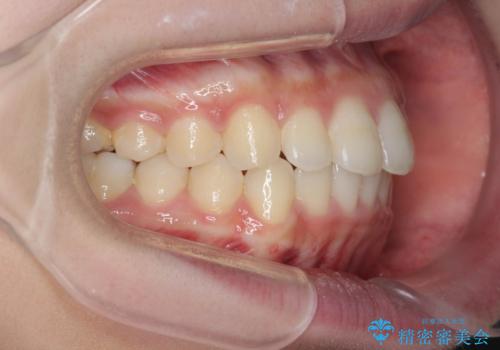

出っ歯を治すマウスピース矯正

- 出っ歯のように見える前歯の角度を治したい、と矯正治療を希望され来院されました。

抜歯をせずにマウスピース矯正システムインビザラインを用いてしっかりと前歯の角度を改善していきます。

前歯の角度だけでなく内側に倒れ込んでいた奥歯もしっかり起こすことで咬合関係も理想的に仕上げています。